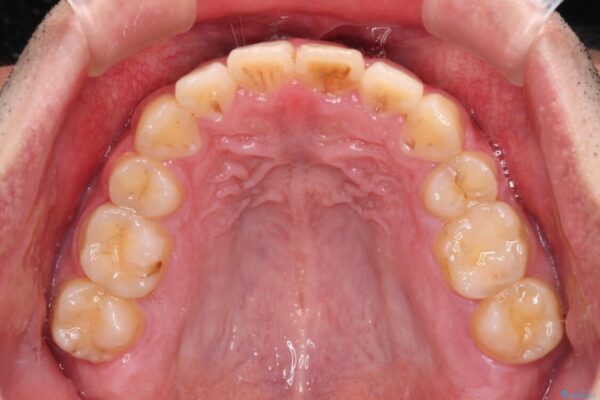

治療後

• 後戻りでデコボコの前歯 インビザライン矯正治療 治療後画像